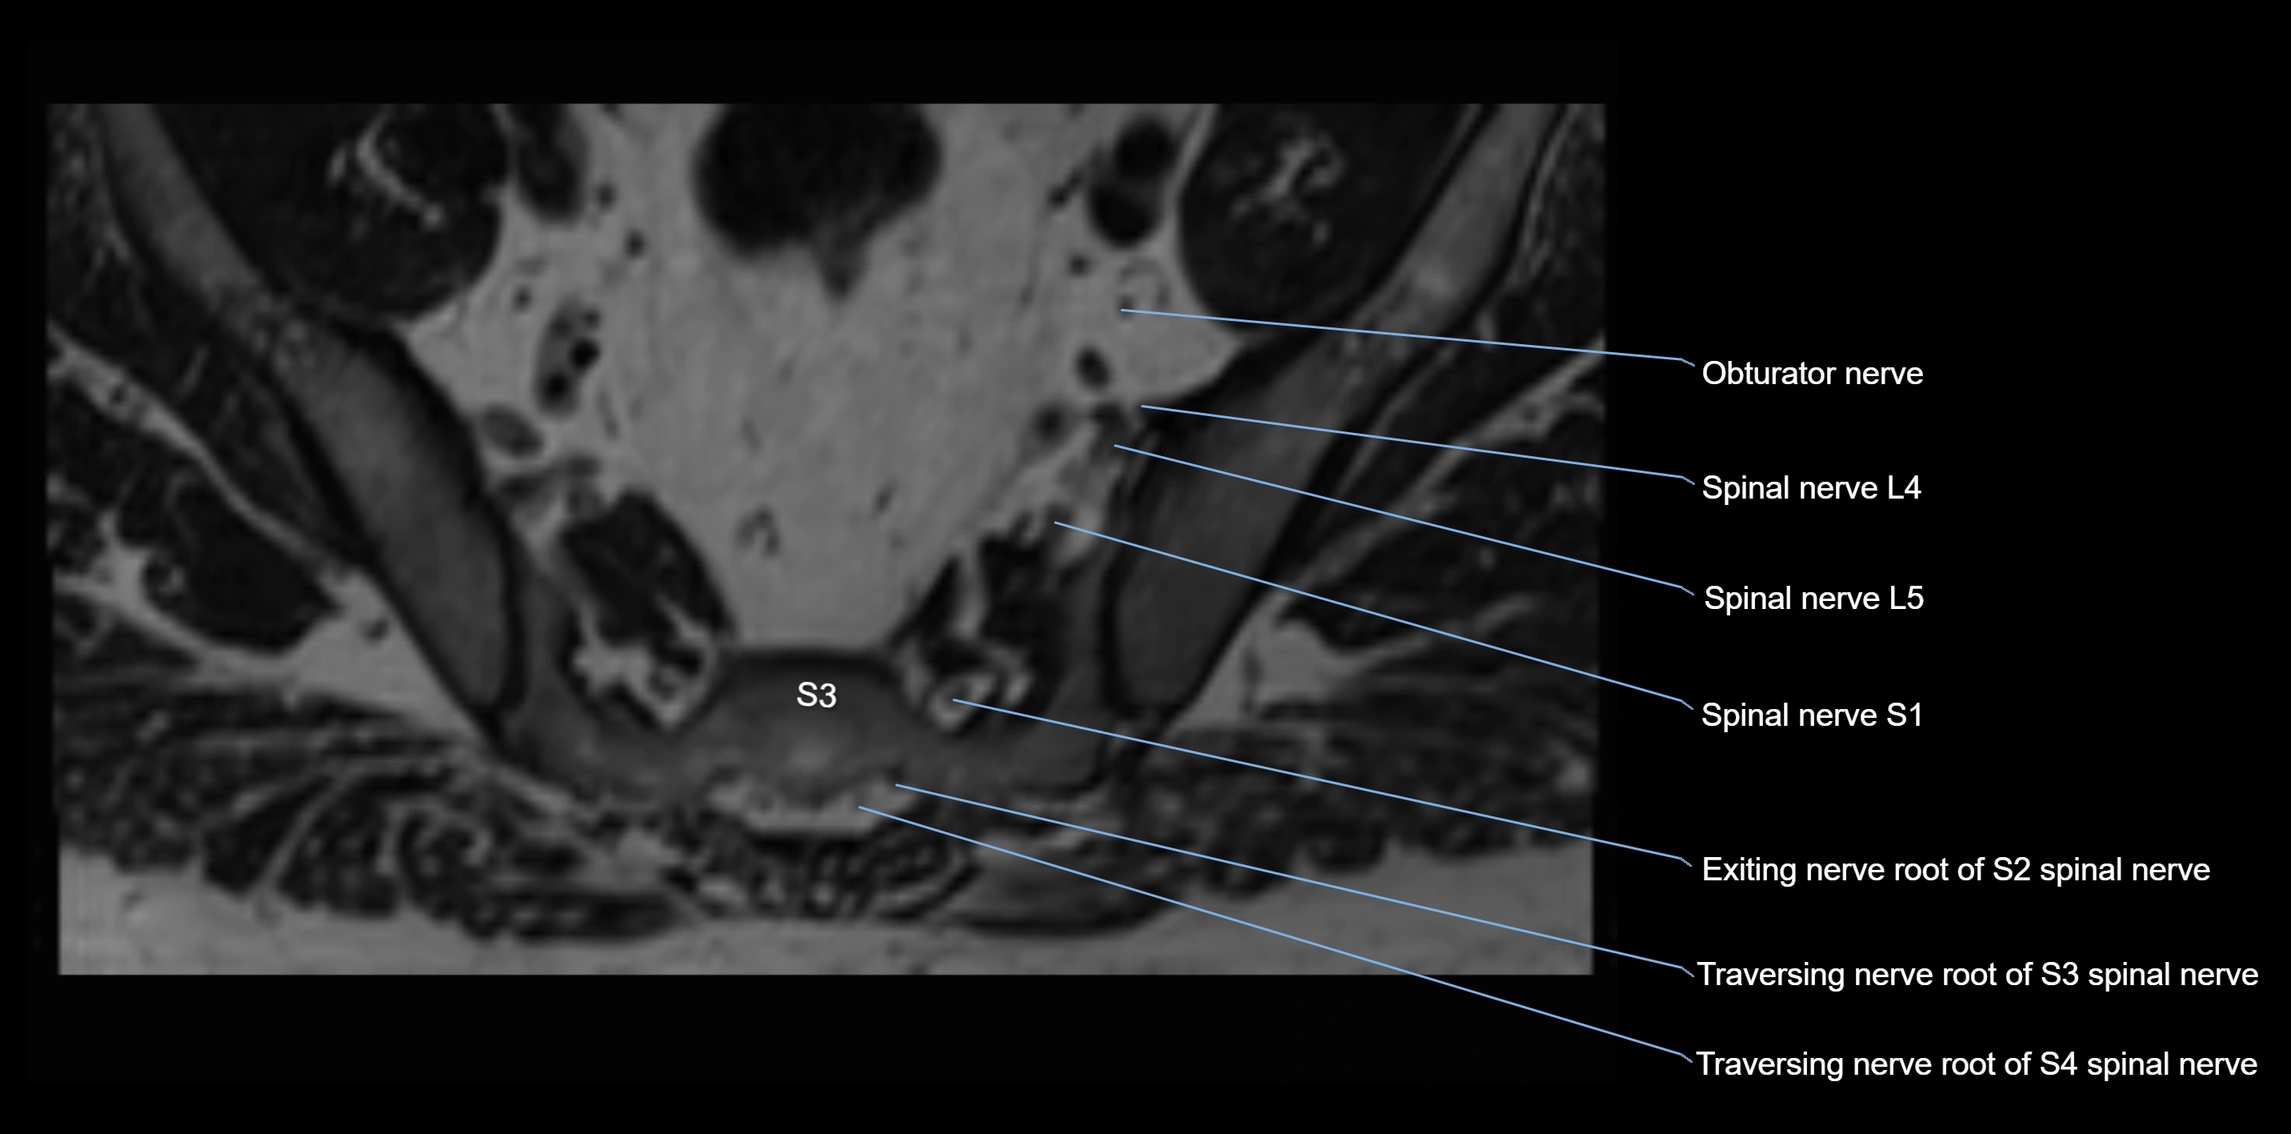

MRI image

image